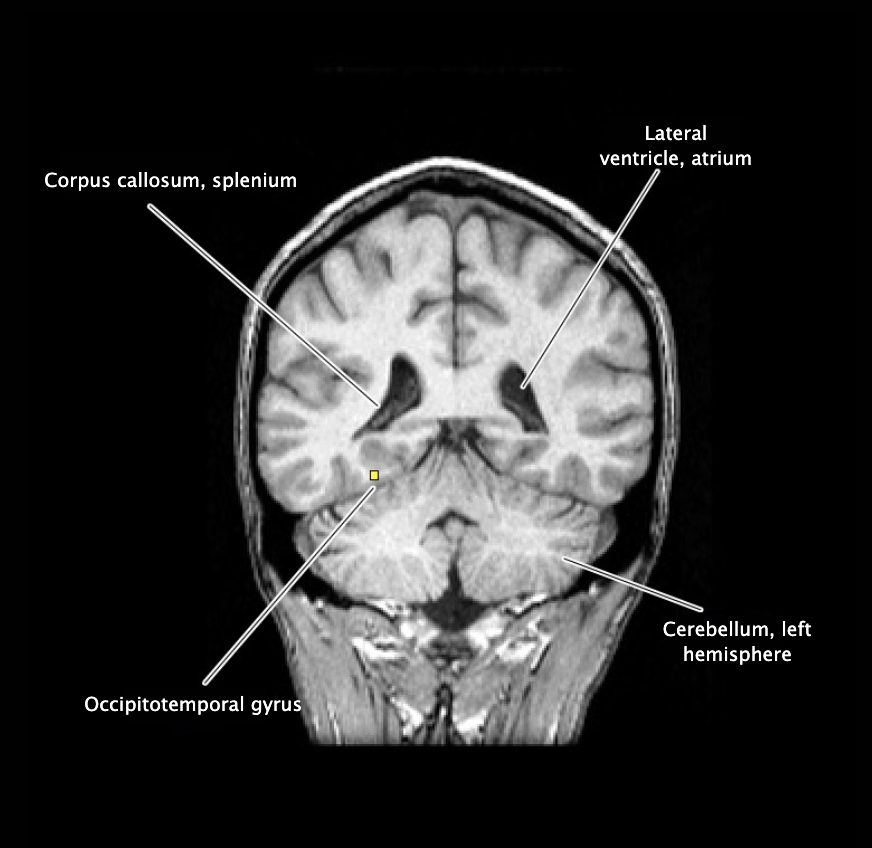

Occipitotemporal gyrus

Longitudinal gyrus on the inferior surface of the temporal and occipital lobes, bounded by the collateral sulcus medially and the lateral occipitotemporal suicus laterally.